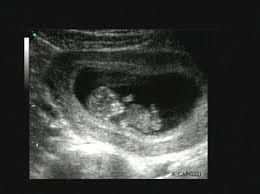

- Ecografia ostetrico-ginecologica

- Ecografia in gravidanza con valutazioni morfologiche

Ecografia Ginecologica/Ostetrica. Utilizziamo sonde dedicate (fino a 13 mhz) per visualizzazioni superficiali e profonde, inclusi studi avanzati 3D e 4D. L'ecografia mammaria, spesso integrata con la visita senologica e la mammografia (pacchetto senologico), è un pilastro della nostra attività di screening. I nostri specialisti garantiscono l'affidabilità della